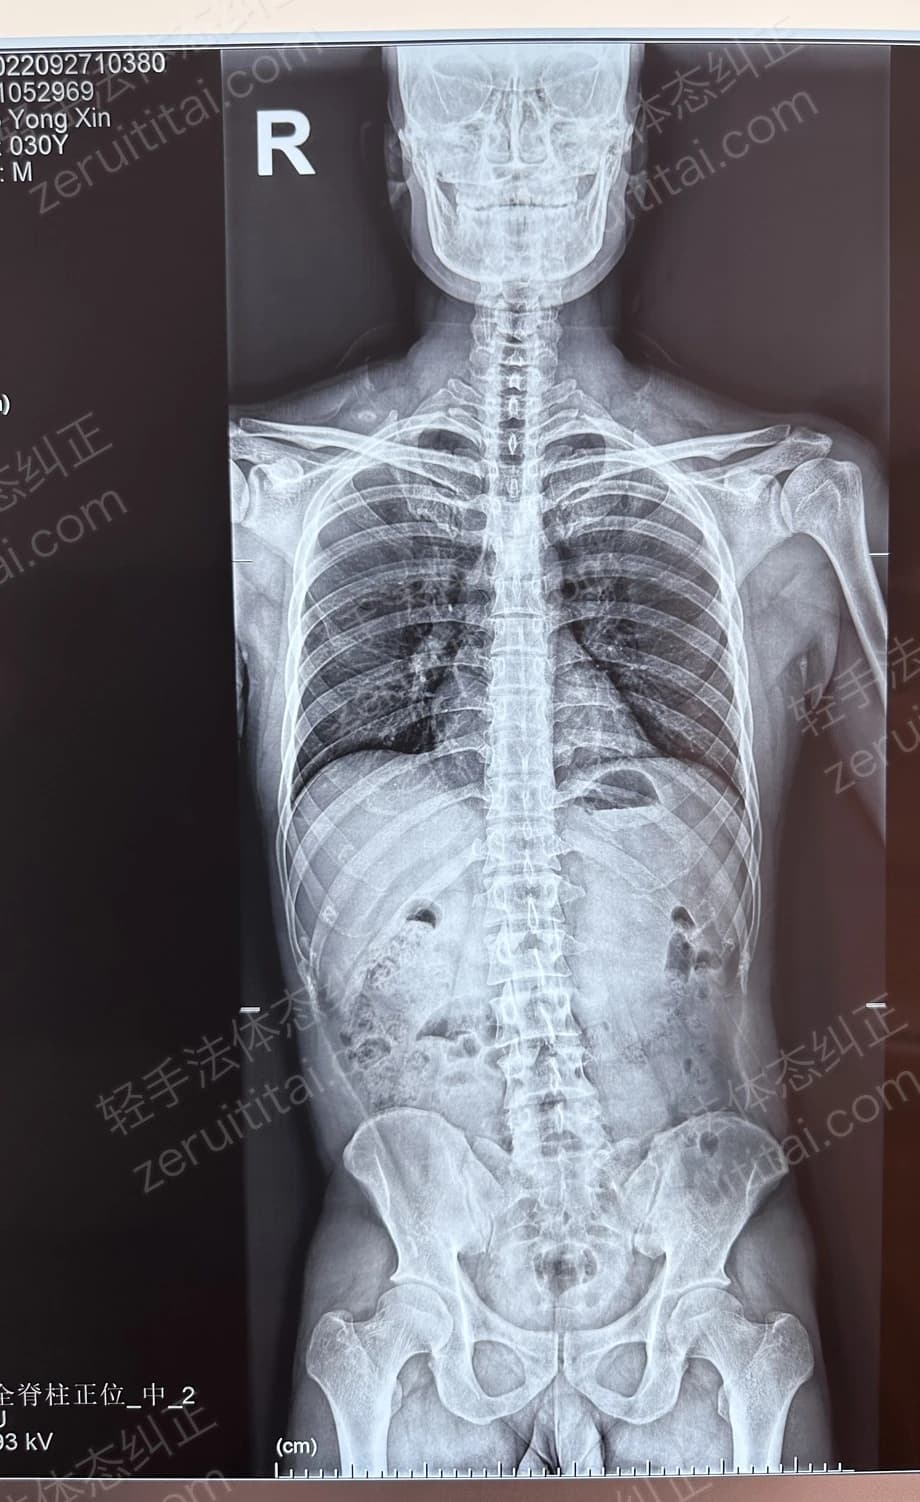

2022.09.27

第 2 次记录